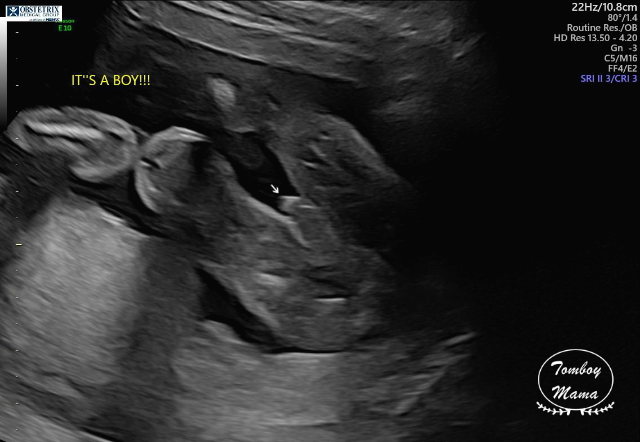

여기서 잠깐 보고 가는 튼튼이 20주차 (정확히는 19주 6일차) 초음파 사진들!

(1) 태아도 건강하고, 크기도 딱 좋고 (하루만큼 더 커서 20주 0일 크기), 다 좋단다.

(2) 단, 태아의 뇌에 낭종(choroid plexus cyst)이 있는데, 주로 다운증후군과 연관이 있는 증상이라고 했다. 자연스럽게 사라질 수도 있는 거고, 아이큐에 영향을 준다던가 하는 그런 문제가 아니기 때문에, 이게 발견되었다고 나중에 따로 추적하지는 않는다고 했다. 다만 다운증후군 가능성이 염려되면 (바늘로 찔러서 하는) 양수 검사를 할 수 있는데, 솔직히 지금 나에게는 추천하지 않는다며 3가지 이유를 얘기했다.

a. 정밀 초음파 검사 결과 이 외의 다른 증상이 보이지 않고, 모두 정상으로 보임.

b. 아기의 크기가 정상적으로 잘 자라고 있음.

c. NIPT 및 NT 테스트 결과가 이미 음성이었음.